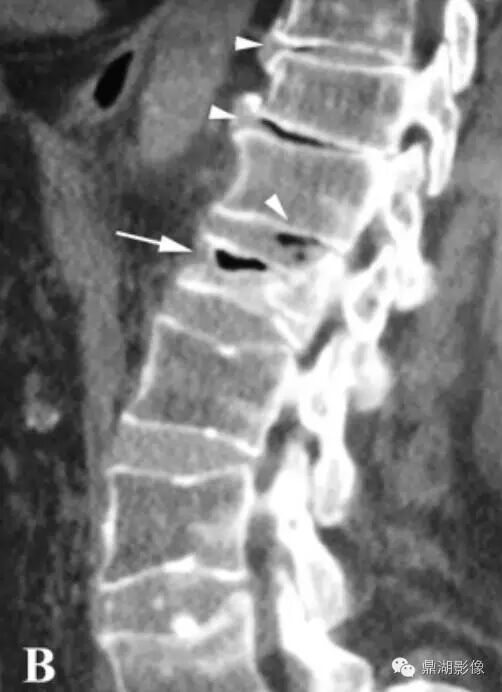

CT:可以看到真空征,同时骨质表现出蛋壳样改变。

真空裂隙征(IVC):是椎体缺血坏死的典型表现,前部较后部多见;IVC为渗液时,T1低信号,T2高信号,此征象称为液体征象,高度提示椎体缺血坏死,并可用于鉴别kummell与骨质疏松引起的压缩性骨折,IVC为气体时,MRI均为低信号。

T2WI,双线征(线样高信号被低信号包绕)